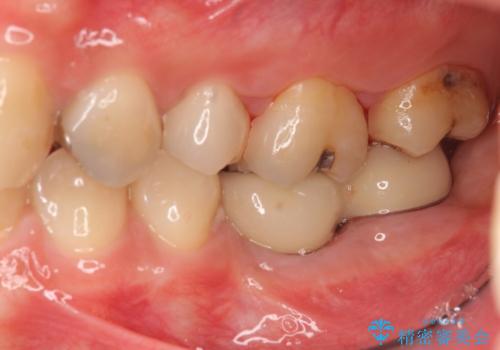

他院で断られた骨造成を伴うインプラント治療

- 80万円(インプラント×2・骨造成・アバットメント×2)・ジルコニアクラウン×2)費用は治療当時の料金となります

インプラントの長期的な予後を見込むには、インプラント周囲の安定した十分な骨量や清掃性、角化歯肉の存在が重要です。